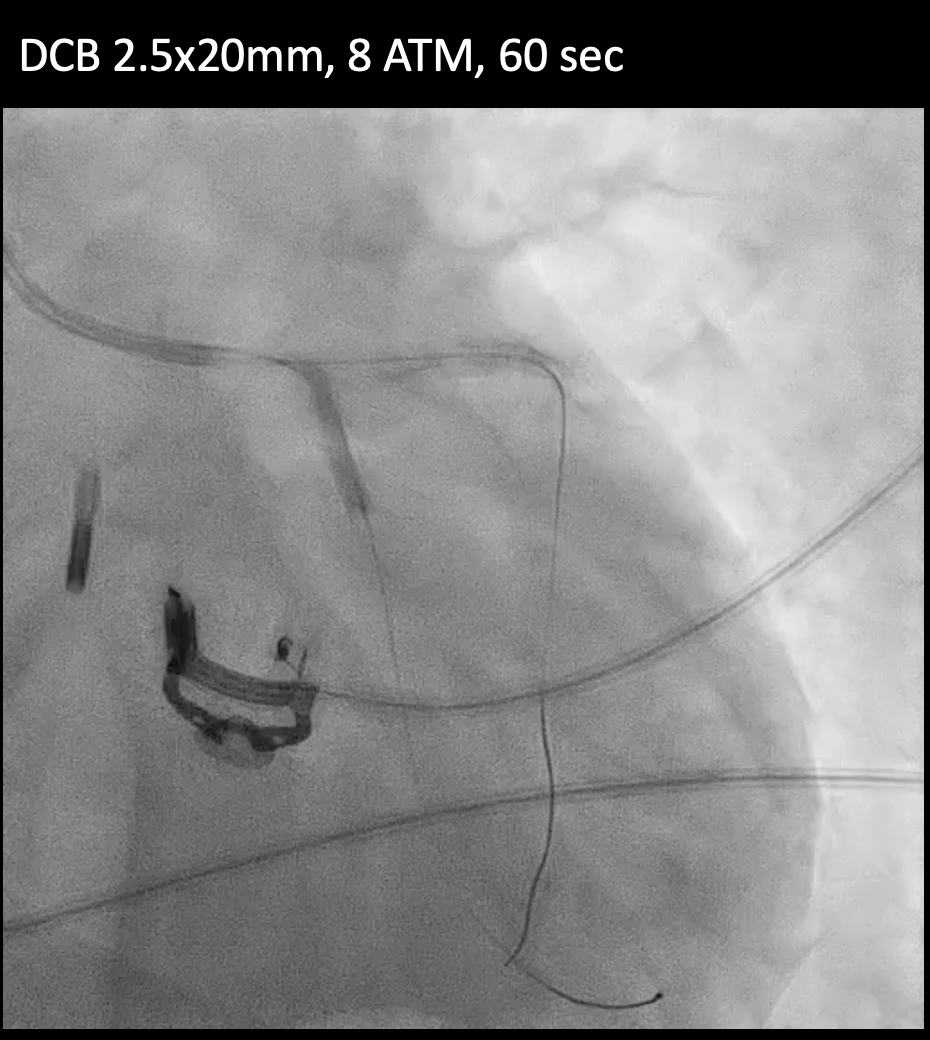

Under IABP (left femoral), PCI via right brachial with 6 Fr EBU 3.5. Runthrough to LAD, Sion Blue to LCX. Predilation of LM/pLAD with 2.0¡¿20 mm balloon; IVUS pullbacks. Further dilatation with 2.5¡¿20 mm NC for mLAD underexpansion, pLAD, and LM. oLCX de novo and pLCX edge ISR predilated with 2.5¡¿20 mm NC; LCX ISR treated with DCB 2.5¡¿20 mm. Szabo technique attempted for LM–LAD with a 3.0¡¿24 mm DES; the undeployed stent dislodged during repositioning and was deployed at the dislodgement site. IVUS showed 2–3 struts protruding into the aorta from the LM ostium and incomplete pLAD coverage. Post-dilation with 3.5¡¿20 and 2.5¡¿20 mm NC; DCB 3.0¡¿20 mm for pLAD uncovered plaque and mLAD proximal edge ISR. Final CAG: TIMI 3 flow.At 3 months, staged PCI via right radial with 6 Fr EBU 3.5. Sion Blue ES to distal LAD. IVUS: mLAD stent underexpansion (MSA <2.0 mm©÷); wire not through struts. IVL 3.5¡¿12 mm initially could not cross LM; after guide exchange (JL 3.5, then EBU 3.0/3.5), IVL advanced to mLAD and delivered 100 shocks, producing a ring crack and area gain. Further dilation with 3.0¡¿20 and 3.5¡¿20 mm NC. IVUS: pLAD type B dissection without flow limitation. DCB 3.5¡¿40 mm to p–mLAD. LM ostial stent further dilated with 3.5¡¿20 mm. Final CAG: TIMI 3 flow.